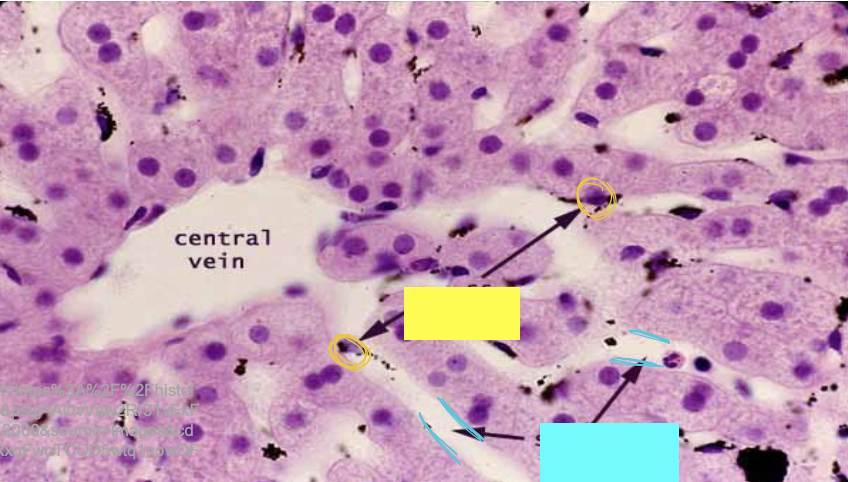

what is the arrow pointing to?

sinusoids

what are the yellow circles indicating?

kupffer cells

what are the blue lines indicating?

what are the yellow lines indicating

bile canaliculi